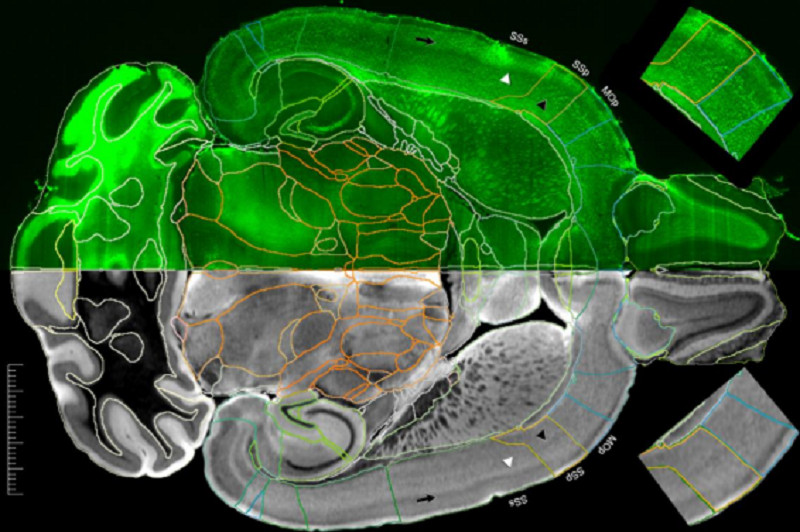

Американские ученые заявили, что смогли получить самые подробные изображения МРТ мозга мыши за всю историю исследований. По их словам, разрешение этих изображений в 27 тысяч раз превышает качество предыдущих.

Группа ученых из разных американских университетов опубликовала в журнале Proceedings of the National Academy of Sciences результаты исследования и рассказали, как добились самого подробного МРТ-изображения мозга грызунов за всю историю наблюдений.

Исследователи обратили внимание на то, что в 1973 году, когда миру только-только представили «Создание изображения с помощью индуцированного локального взаимодействия», это самое изображение больше напоминало пиксельную восьмибитную графику.